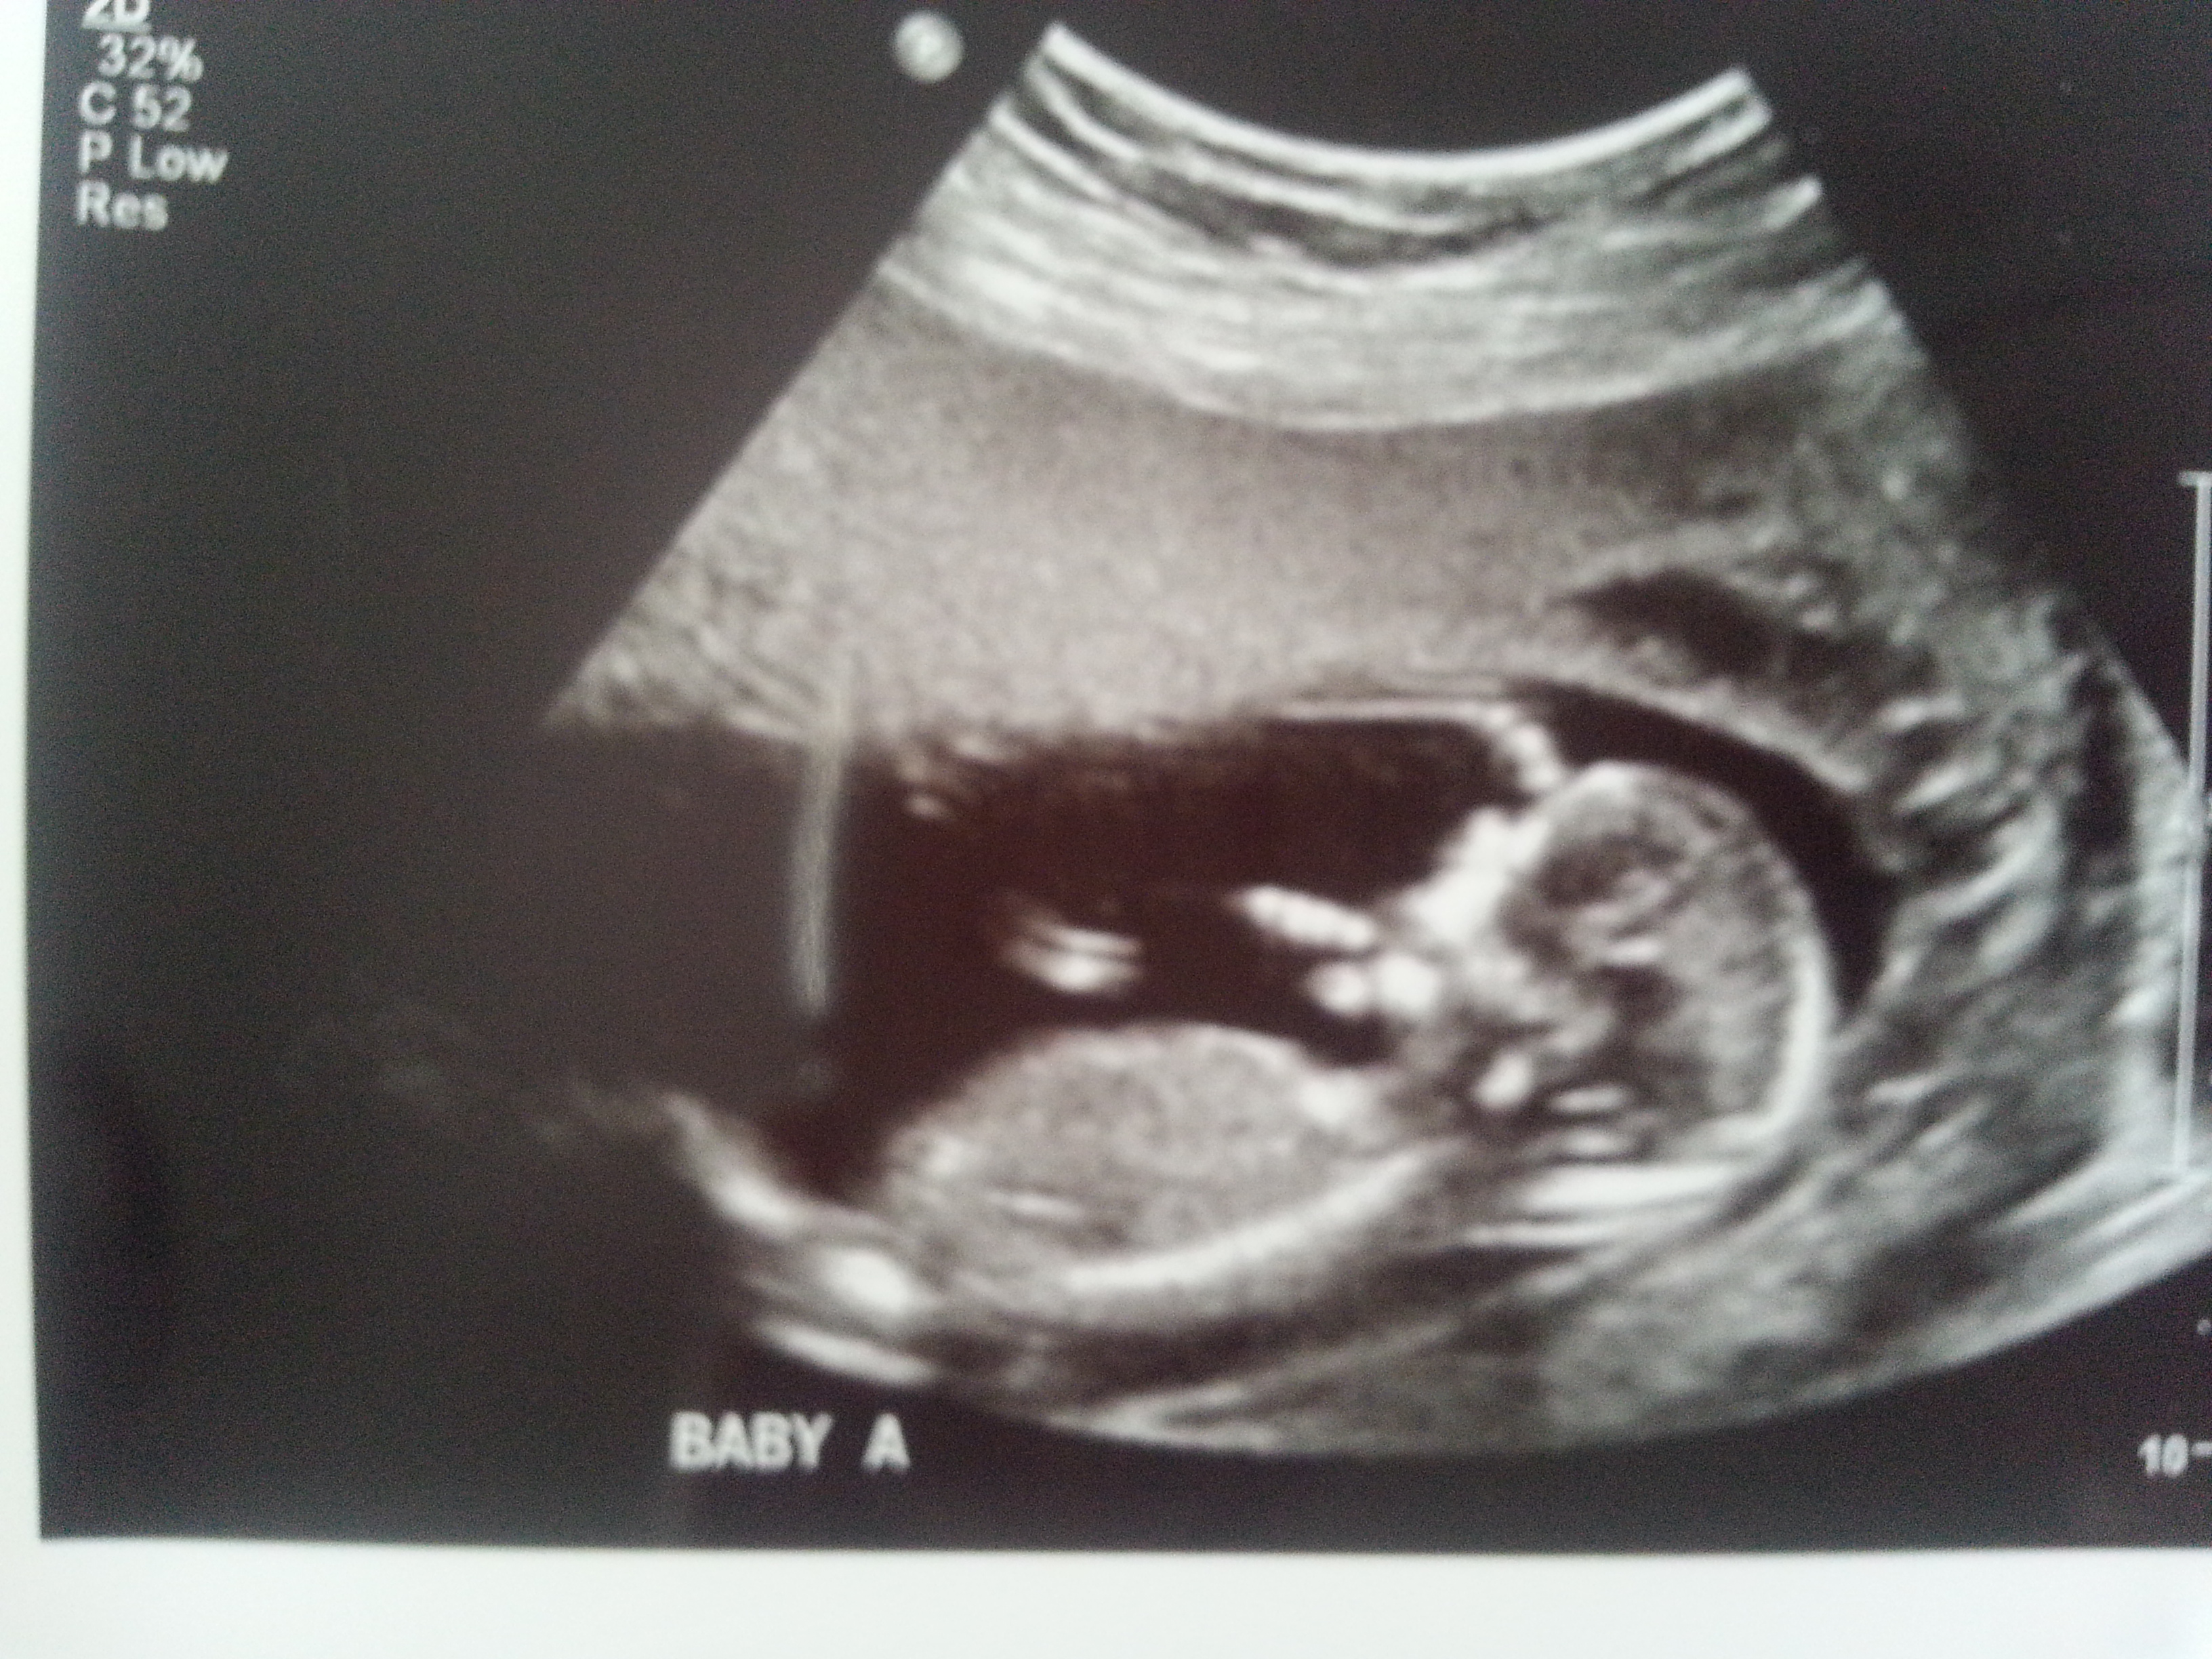

I was 12weeks 6 days and measuring 13weeks 3 days.

Maybe boy/girl. Not the best shots though!

I think B is a boy and A is a girl.

I'd guess boy/girl too. Baby B looks really boyish. Baby A is more questionable, but at 13 weeks, I'll lean girl.

I definitely see the girly nub for baby A now thanks to Nahris post!

I think B is def a boy. A has a boyish skull but girly nub. I'd go with the nub though and lean girl! Congrats on your twins!